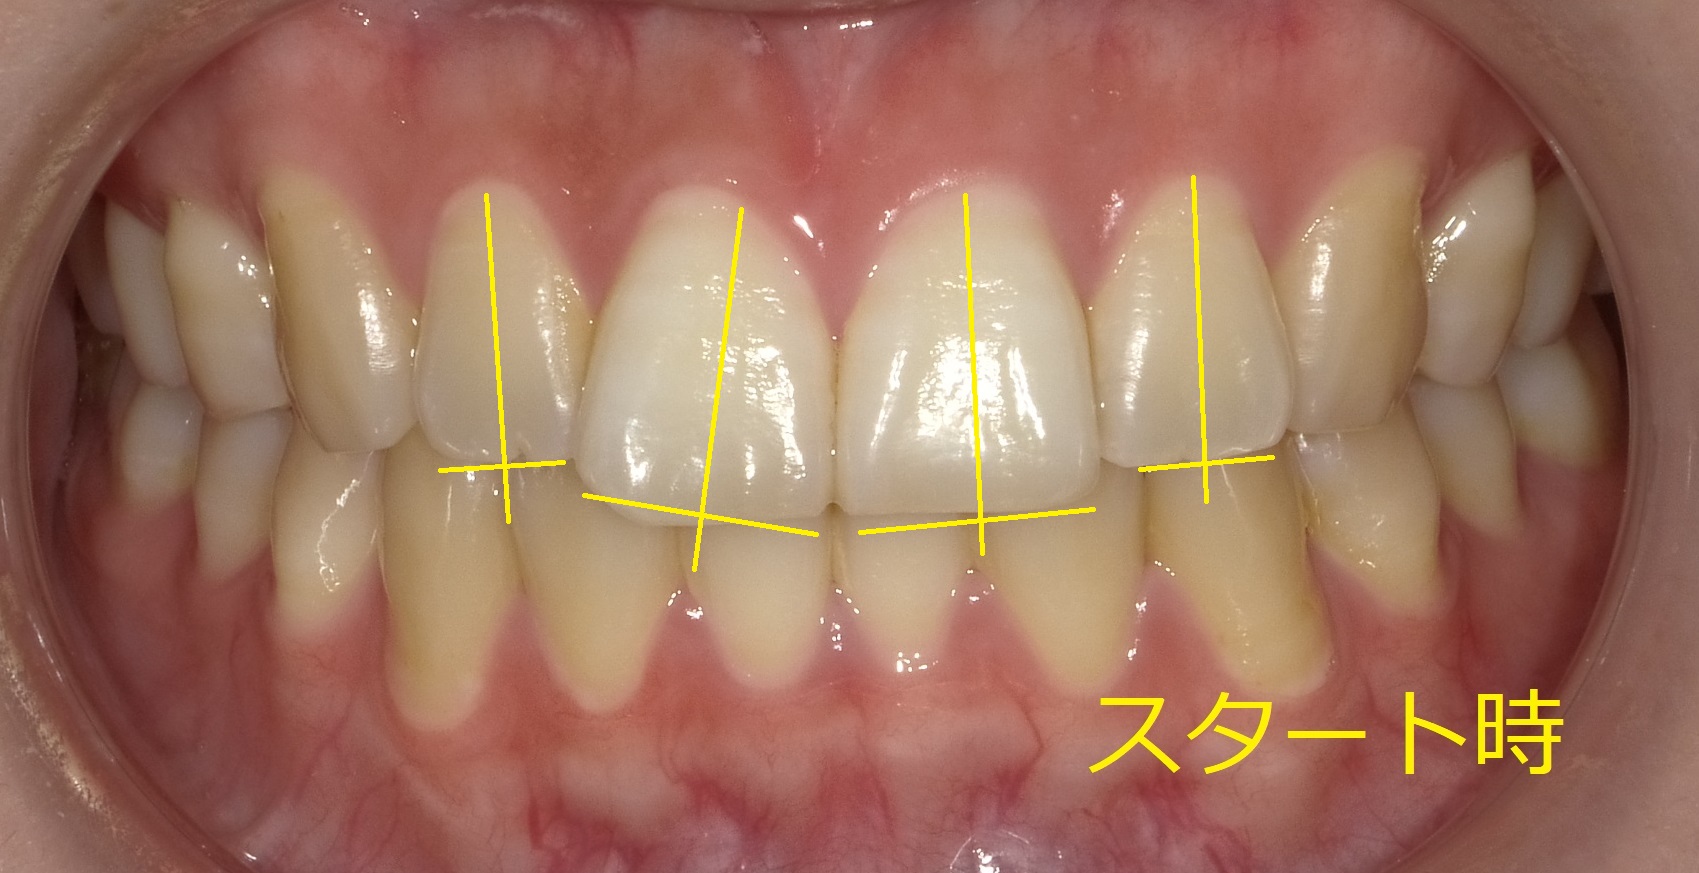

アップの写真ではあまりズレが分かりづらいので、実際の軸を写真に書き加えてみます。

歯の軸と、それに対する先端のラインを書き込むことで、

「並びのズレ」と「歯の不均等な摩耗」がハッキリします。

①左上1,2番目の歯が全体的に斜め前に突出している(けど、あまり分からない)

②右上1番前歯は歯並びから大きく外れて右斜め前に前突している。

③上2番目の歯は1番前歯が斜め前にズレているおかげで内側(中心よりに傾いている)